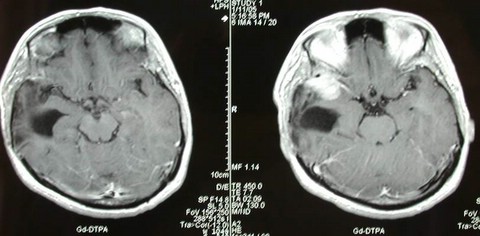

女性,29岁,主因头痛恶心呕吐1个月入院。查MRI示:右侧中颅底巨大脑膜瘤。

术中显微手术全切肿瘤。术后无加重神经功能障碍。术后图片如下: